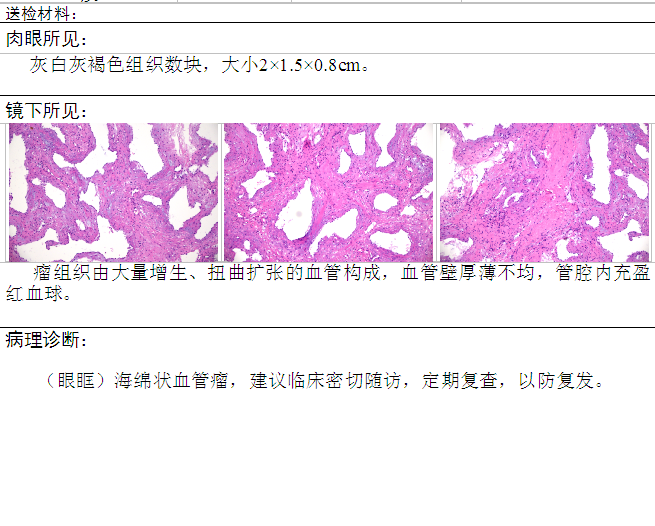

病理诊断:

病理诊断: